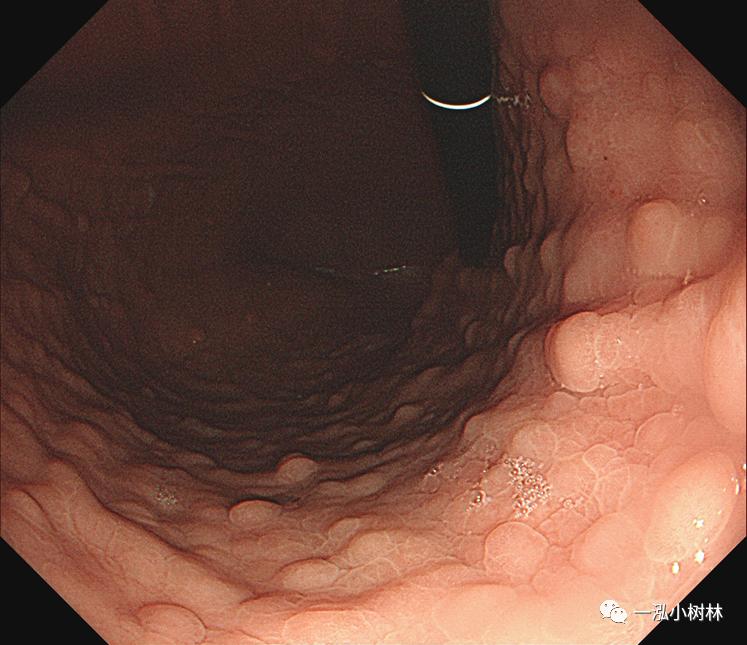

F 23,上腹部不适1年。

白光内镜:胃体多发息肉